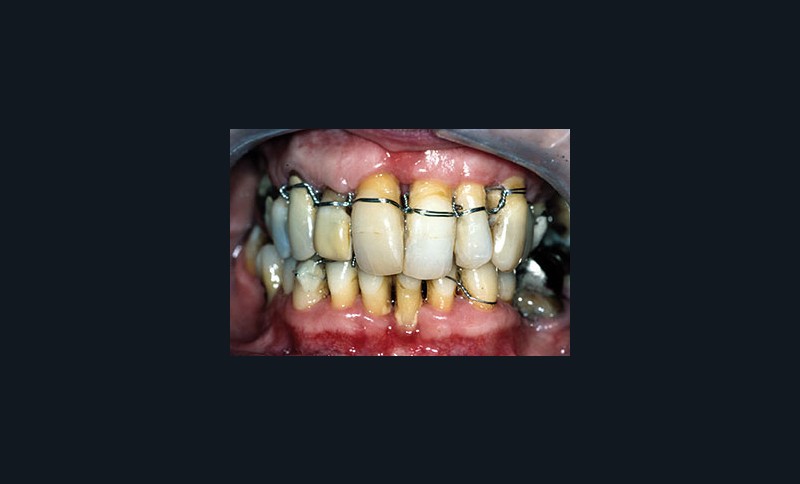

Une patiente âgée de 45 ans consulte à la fin des années 1990 avec une contention en échelle au maxillaire afin de soulager les mobilités des dents antérieures.

Les examens cliniques et radiographiques montrent une parodontite chronique généralisée (fig. 1a à m).

La patiente, en bonne santé, ne fume pas.